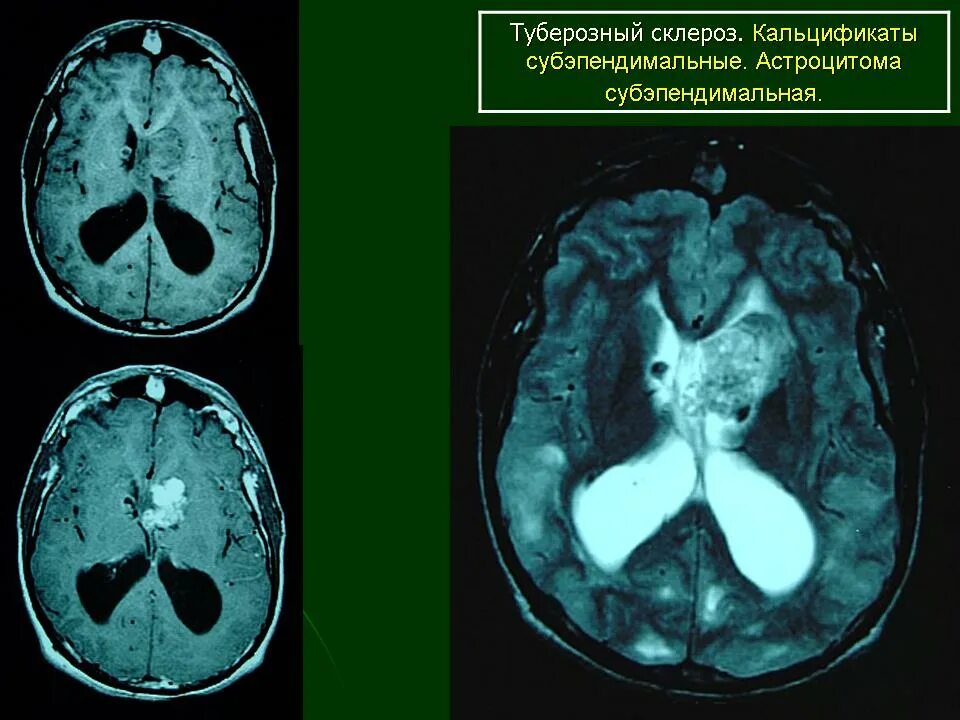

Туберкулезный склероз